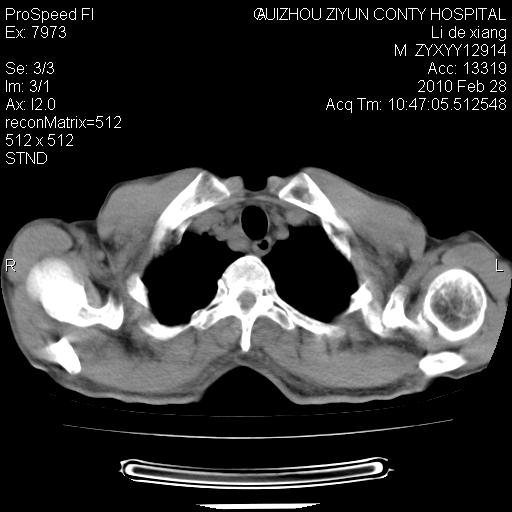

标题: CT24776:男 71Y 咳嗽咳痰胸痛两月,伴声音嘶哑。 [打印本页]

标题: CT24776:男 71Y 咳嗽咳痰胸痛两月,伴声音嘶哑。

患者有声音嘶哑,若时间长了,没改变,喉镜检查无异常,可考虑左侧喉返神经受累,因为:左侧喉返神经绕主动脉弓或肺动脉韧带的主动脉端,沿气管与食管之间的沟上行至颈部.

支持肺癌.

左上叶支气管狭窄,阻塞性病变,肺门肿块,纵隔及肺门淋巴结增大,中央性肺癌

左肺中央型肺癌并阻塞性改变、纵膈 淋巴结转移